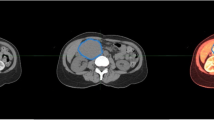

The workflow of the radiomics analysis included image segmentation, feature extraction, radiomics signature modeling. and model analysis (Fig. 1).

CT image acquisition, segmentation, and feature extraction

All arterial and portal venous phase CT images were retrieved from a picture archiving and communication system (PACS) for further analysis. The procedure of CT image acquisition, segmentation, reproducibility analysis, and feature extraction are described in Supplementary Information 2.